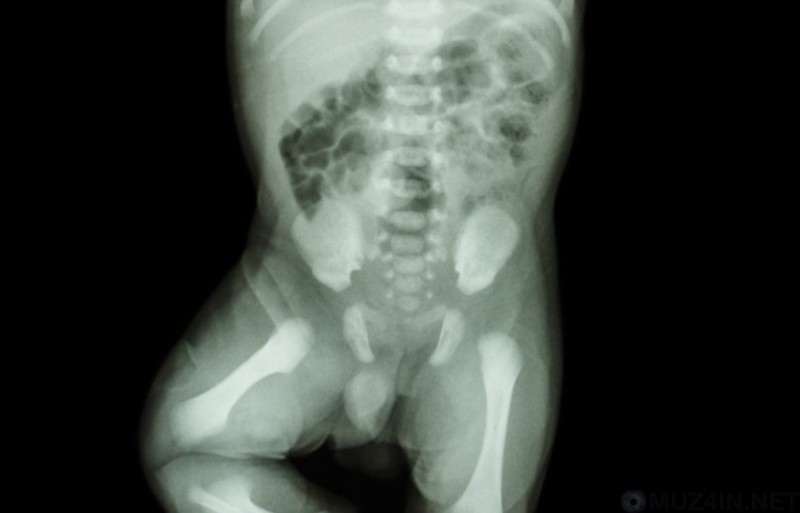

№15. Детские рты — жуть

Рентгеновские снимки детских ртов — готовый материал для фильмов ужасов. На снимках видно, что коренные зубы, который однажды вылезут на место молочных, расположены вторым рядом прямо в черепе.